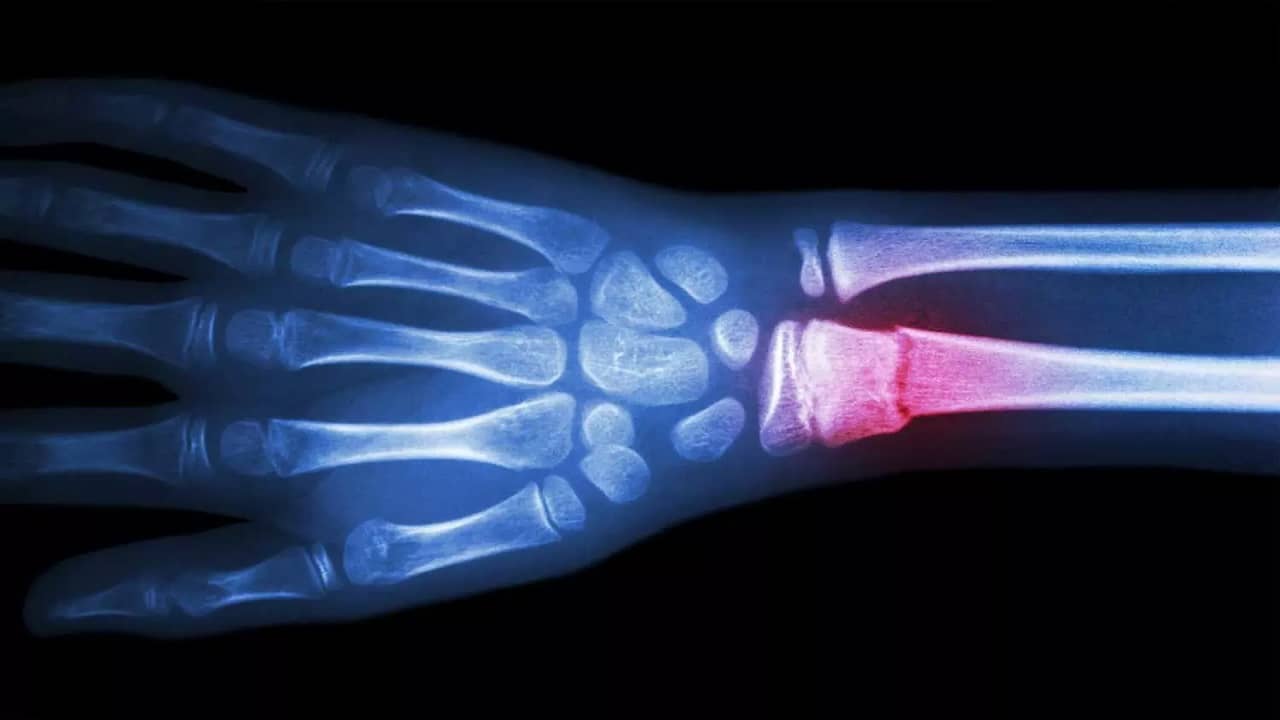

New Scientific Study: পরিবেশ দূষণকে কেন্দ্র করে বিজ্ঞানীরা (Scientists) একের পর এক সতর্ক বার্তা দিয়ে চলেছেন। আর যে হারে বিশ্ব উষ্ণায়ন (Global Warming) দিনের পর দিন বেড়েই চলেছে, তাতে পরিবেশ দূষনকে আটকে রাখা ক্রমশ অসম্ভব হয়ে পড়ছে। মানুষ যত উন্নত হচ্ছে, ততই পরিবেশের অবস্থা খারাপ রূপ ধারণ করছে। আর সেই সঙ্গে বাড়ছে বায়ু দূষণের (Air Pollution) মাত্রা। বায়ুতে বিষাক্ত গ্যাসীয় ও সূক্ষ্ম ধূলিকণা মানুষের শ্বাস ক্রিয়াকে প্রভাবিত করে। কার্বন মনোক্সাইড গ্যাসটি মানুষের ফুসফুসে প্রবেশ করে, রক্তের হিমোগ্লোবিনের সঙ্গে বিক্রিয়া করে কার্বক্সিল হিমোগ্লোবিন গঠন করে। ফলে মানুষের রক্তে অক্সিজেন বহন করার জন্য প্রয়োজনীয় হিমোগ্লোবিনের পরিমাণ হ্রাস পায়। কিন্তু আপনি কি জানেন, আপনার শরীরে হাড়ের ক্ষয় হয়, বায়ু দূষনের ফলে। নতুন এক গবেষণায় এমনই ভীতিকর বিষয় সামনে এসেছে। অর্থাৎ আপনি যত বেশি বায়ু দূষণযুক্ত শহর বা এলাকায় বাস করবেন, আপনার হাড় তত বেশি দুর্বল হবে। অস্টিওপোরোসিসের মতো দুরারোগ্য রোগ বাসা বাঁধবে আপনার শরীরে। হাড় এতটাই ভঙ্গুর হয়ে যাবে যে, সামান্য আঘাতেই তা ভেঙে যাওয়ার সম্ভবনা থাকবে।

বিজ্ঞানীরা সতর্ক করে জানিয়েছেন, যত বেশি দূষণের মাত্রা বাড়বে, মহিলাদের হাড় ততই দুর্বল হতে থাকবে। নিউইয়র্ক কলম্বিয়া বিশ্ববিদ্যালয়ের বায়োমেডিক্য়াল বিজ্ঞানী দিদিয়ের প্রাদা বলেছেন, “একজন ব্যক্তির হাড়ের শক্তি শুধুমাত্র তার খাদ্যের উপর নির্ভর করে না। বরং সে কোথায় থাকে, আবহাওয়া কেমন, দূষণ কত, এই কারণগুলিরও একটি বড় অবদান রয়েছে। যেসব শহরে বায়ু দূষণ বেশি, সেখানে হাড় ভাঙার ঝুঁকি বেশি।”

প্রাদার গবেষণা অনুসারে, “নাইট্রোজেনের সঙ্গে যুক্ত দূষণকারী উপাদানগুলি মানুষের মেরুদণ্ডের উপর সরাসরি প্রভাব ফেলে। বায়ু দূষণের কারণে গত তিন বছরে মেরুদণ্ডের সমস্যা 10 শতাংশ বৃদ্ধি পেয়েছে। মেরুদণ্ড খনিজ পদার্থের ঘনত্ব 1.22 শতাংশ কমেছে। বায়ু দূষণের কারণে হাড়ের কোষ দ্রুত মরতে শুরু করে। অক্সিডেটিভ স্ট্রেস তৈরি হয়, যার কারণে বিষাক্ত উপাদানগুলি হাড়ের মধ্যে দ্রবীভূত হতে শুরু করে।” কিন্তু দিদিয়ের প্রাদার দল প্রথমবারের মতো প্রমাণ পেয়েছে যে, নাইট্রোজেন অক্সাইডের কারণে মেরুদণ্ডের হাড়সহ শরীরের অন্যান্য হাড়ের অনেক ক্ষতি হয়।